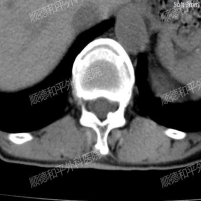

经过询问病史、详细查体及完善腰椎检查后,发现吴阿姨是因为腰椎间盘突出伴神经根的机械性卡压导致左下肢的放射性疼痛。

最终诊断为:“腰椎退行性变、腰椎左凸侧弯畸形、T12椎体压缩性改变、L5/S1椎间盘膨出伴真空变性、多节段椎管狭窄”等复杂腰椎病变,建议手术治疗。

手术过程中,决定采用后入L5/S1椎间盘摘除、L4/5椎间盘植骨融合内固定术治疗。在麻醉科、手术室通力配合下,不到一个小时手术顺利完成。